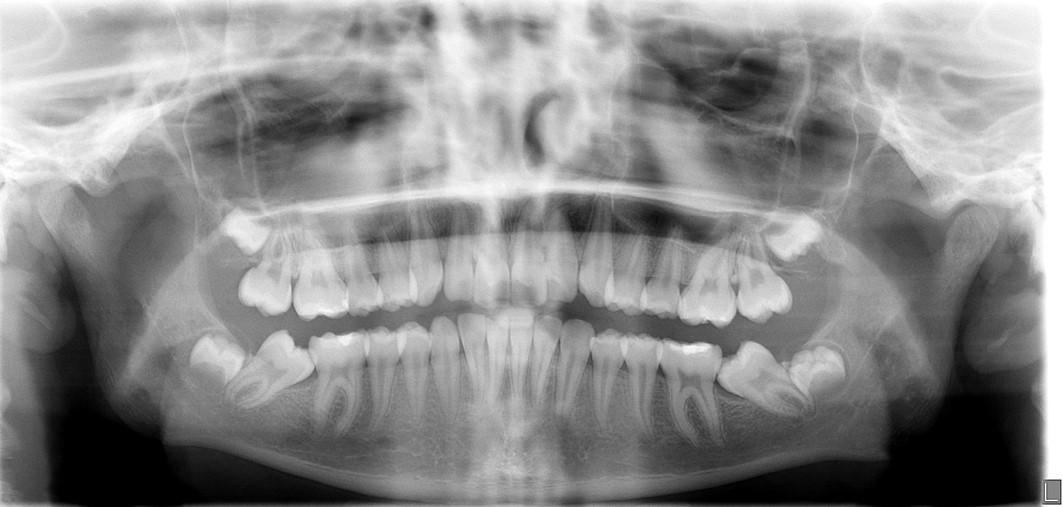

A healthy 12-year-7-month-old female, with an adult dentition, presented with a chief complaint of “teeth not coming in straight,” as was identified to her and her parents by a referring dentist. On clinical examination, the patient had pleasing facial esthetics on an orthognathic skeletal base. Intraorally, the patient had Angle Class I molar relationship bilaterally with well-aligned arches but impacted mandibular second molars with partially visible crowns (Figure 1). The panoramic radiograph confirmed the mesioangular impactions of the mandibular second molars bilaterally along with the third molars at the early crown calcification stage of development (Figure 1). An increase in inclination of second molars can be seen bilaterally, on examination of panoramic radiographs at ages of 10 years and 5 months and 11 years 10 months, which were 17 months apart (Figures 1 and 2).

Fig. 1: Initial presentation of mesioangular impacted mandibular second molars at 10 years and 5 months of age. Note that the mandibular third molars are at about a third crown completion stage of development.only for the understanding purpose.

Fig. 2: Follow-up radiograph at the age of 11 years and 10 months, 17 months after the initial detection of the mandibular second molar impactions. Note that the mesioangular inclinations of both molars had worsened with the further crown development of the mandibular third molar crowns and their positions translating superiorly.